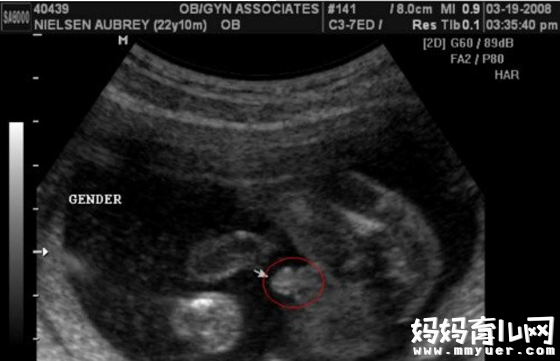

男宝宝B超图

"凸出的东西" 是他的标记: 你们看到圆圆的是DANDAN,如果看到圆圆的加小肠的就是全部JJ